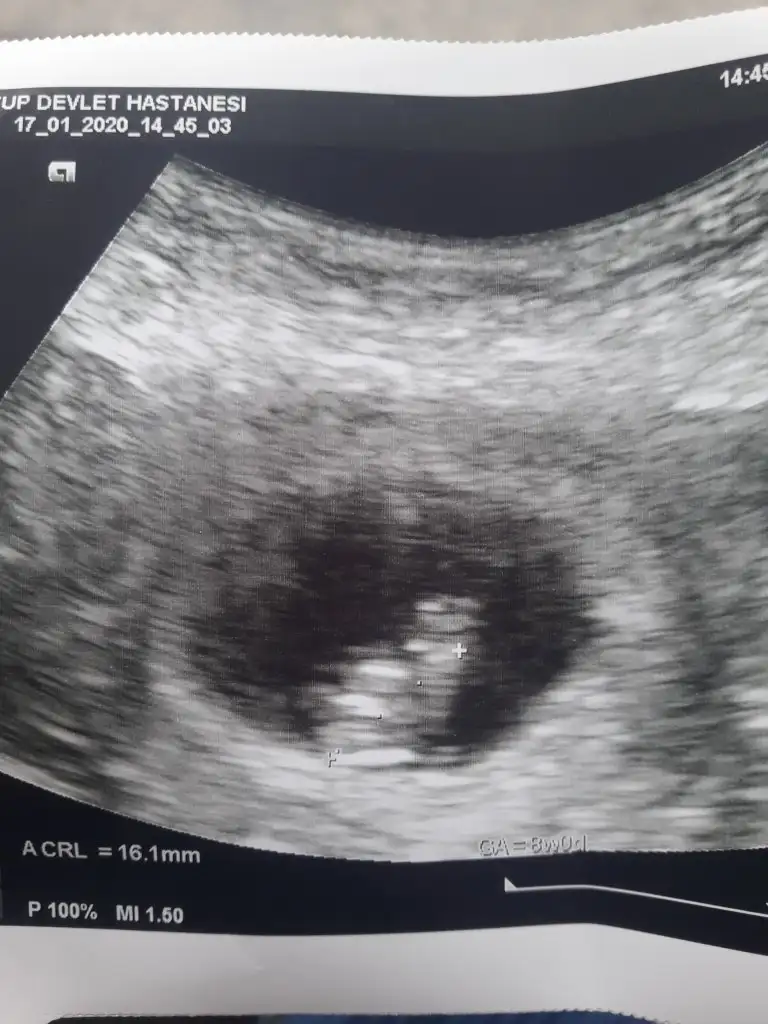

10. Haftadayız. Belki daha erken ama yinede tahmin rica edebilir miyim?😊

Ikra meyra 8 haftalik oldu kaldi 4 hafta bakalim kismet ne olucak.😊

• 20200117_151404.webp

20200117_151404.webp

37,7 KB · Görüntüleme: 39